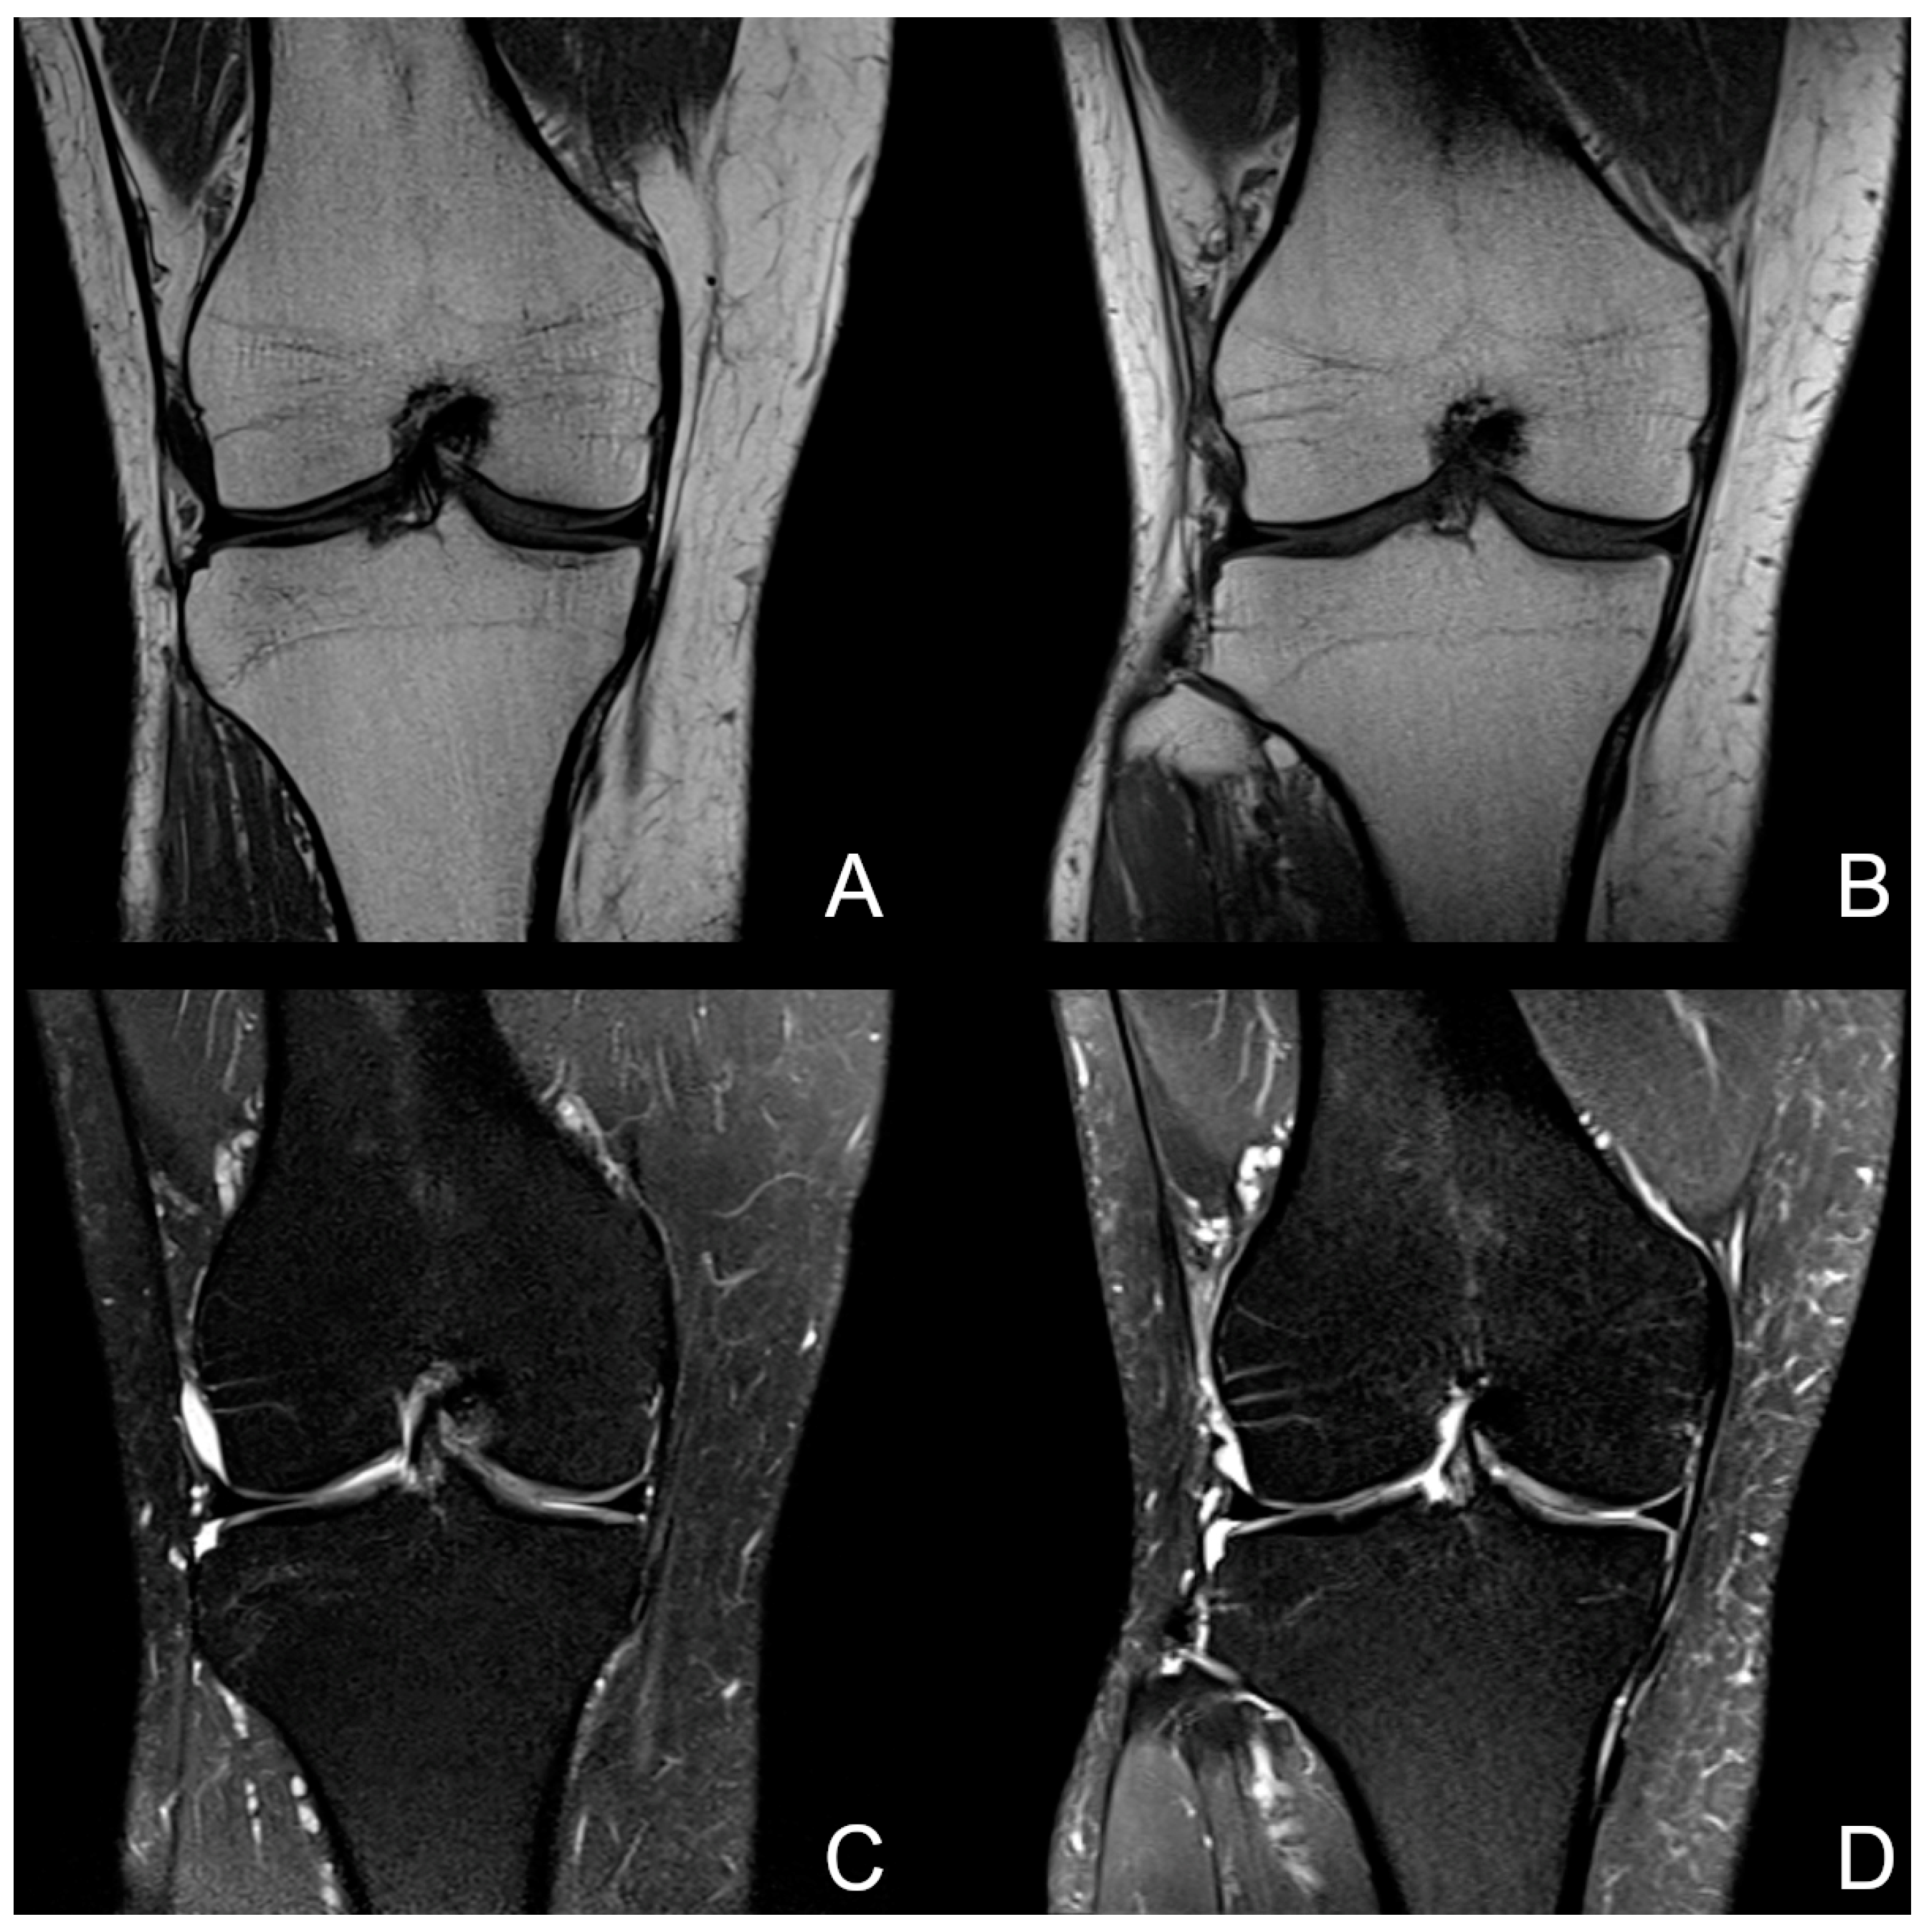

3.2. Visibility of Anatomical Structures and Detected Pathologies